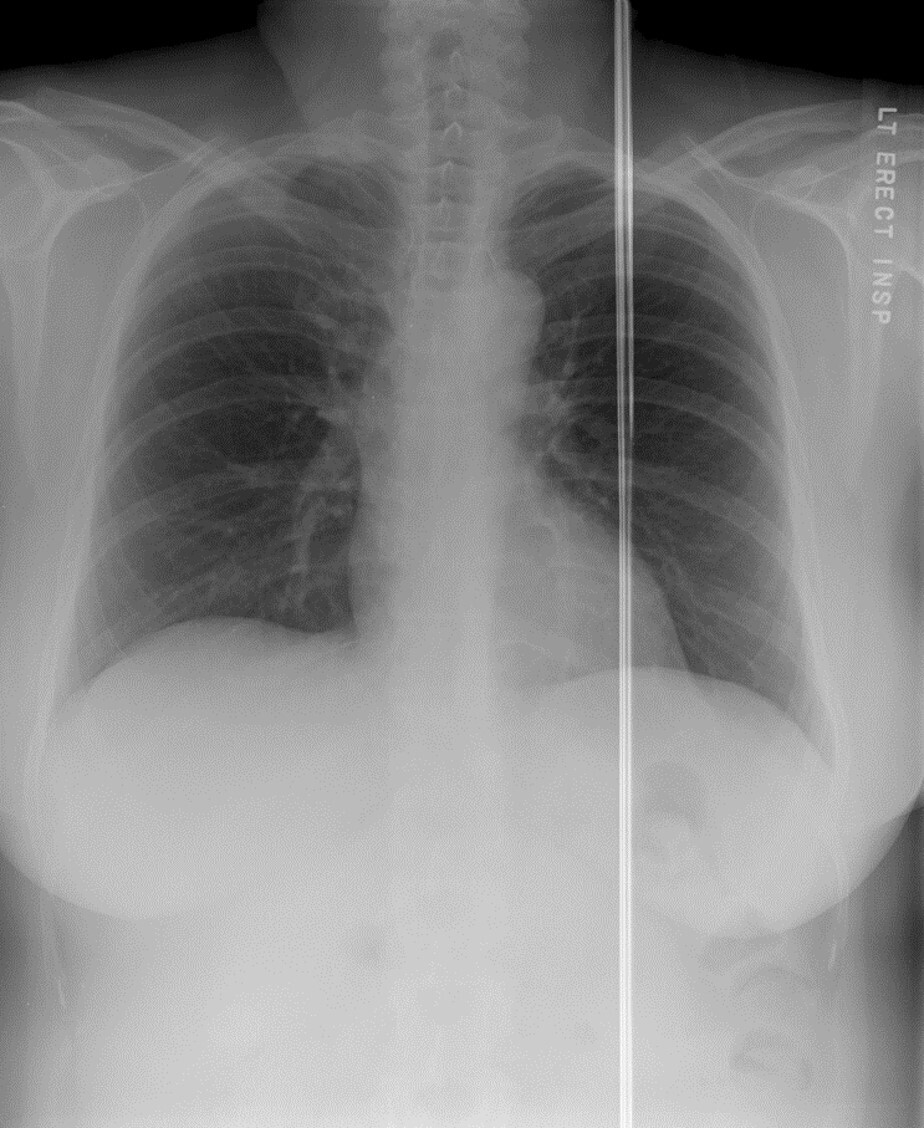

Q

What artifact is seen superimposed over the scapula and lateral chest wall in the attached image?

A

Patient artifact (bra straps)